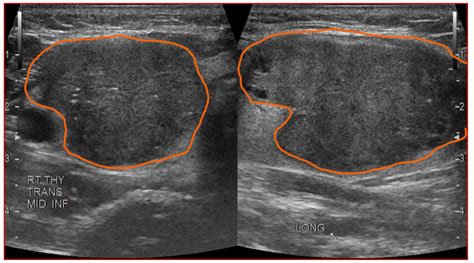

Hypoechoic solid thyroid nodule tirads 4. .